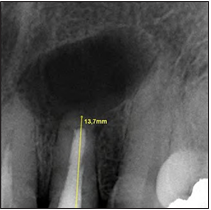

Paciente sexo femenino de 54 años de edad acude a consulta por presencia de fistula en el sector anterior del maxilar, con 15 días de evolución. Durante la anamnesis refiere tener un tratamiento endodóntico de 15 años de antigüedad en el diente 2.2; el mismo tuvo un procedimiento quirúrgico hace 10 años. A la exploración clínica se observó una fístula que se corroboró mediante fistulografía asociada al diente 2.2. La paciente no manifiesta dolor, está asintomática a la palpación y percusión, se realizó un sondaje periodontal obteniendo 3 mm de profundidad. Radiográficamente se observa una zona radiolúcida difusa periapical, cu- briendo el área del diente 2.2, con aproximadamente 13 mm de diámetro, obturación completa del canal radicular, ápice abierto y restauración coronal desadaptada. (Fig.1)

Figura 1. Radiografía periapical inicial.